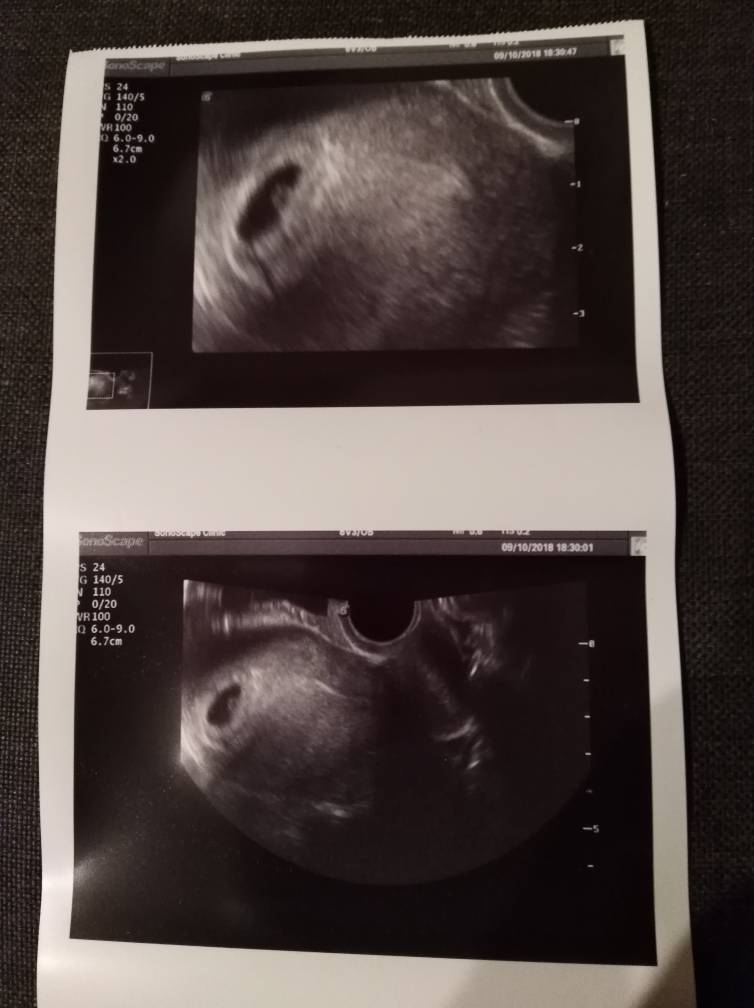

Super gratuluję oby u mnie za dwa tyg na usg też było widaćWrzucam też tutaj pierwsze zdjęcie mojego małego człowieka

GratulujęMoje kolejne szczęścieZobacz załącznik 907823